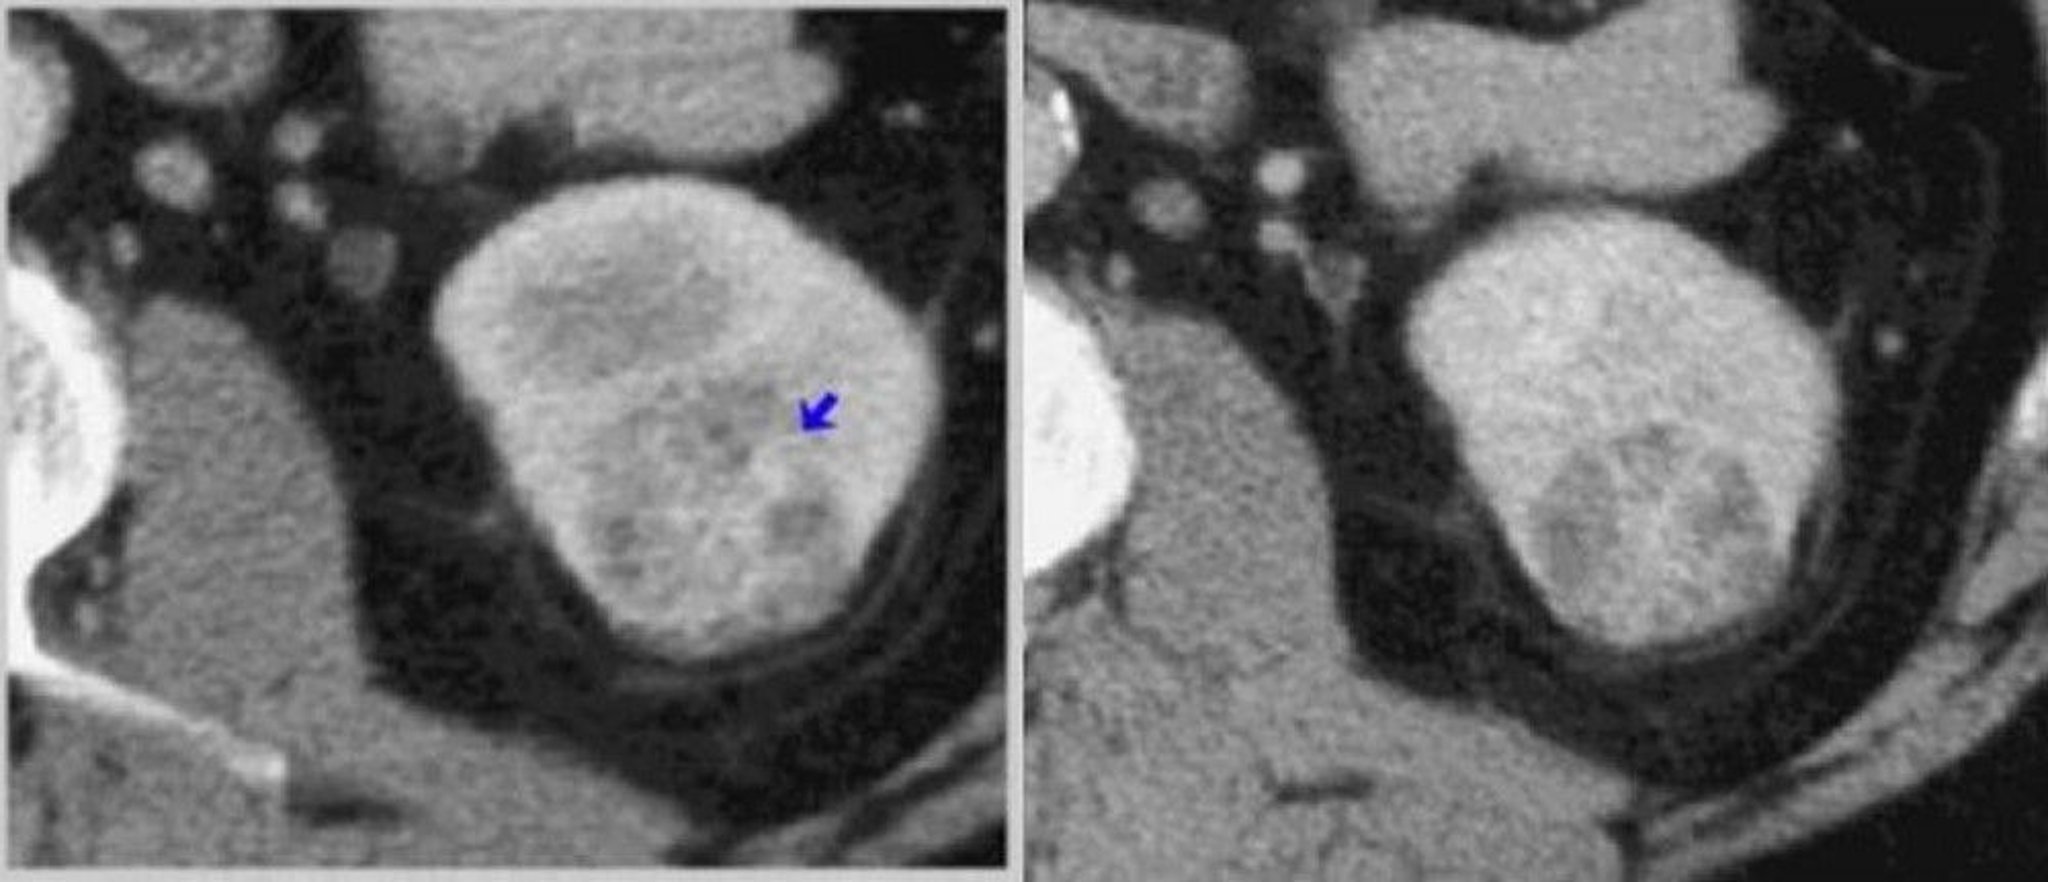

TDM du rein avec contraste (phases corticomédullaire et néphrogénique)

À gauche, une TDM en phase corticomédullaire montre une tumeur prise de contraste hétérogène (flèche). À droite, une TDM en phase néphrographique montre mieux la tumeur.